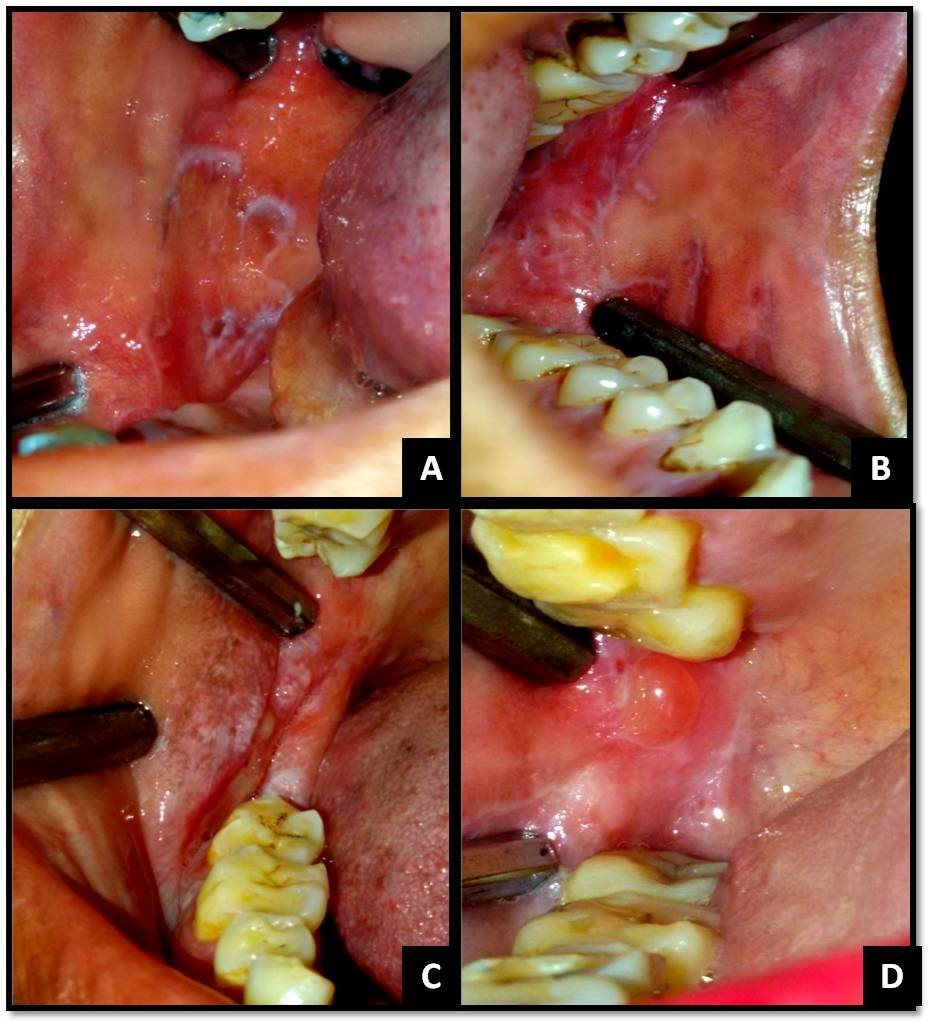

The clinical diagnostic criteria for oral lesions used in this study was- 1. The presence of keratotic, pinhead-sized, white, slightly elevated papules (papular lichen planus), which may be discrete or arranged in reticular (reticular lichen planus) or plaque-like (plaque-like lichen planus) configurations. 2. Atrophic lichen planus, characterized by thinning of the epithelium leading to the appearance of atrophic red areas within the white lesions. 3. Erosive (ulcerative) lichen planus, characterized by areas of well-defined ulceration within the above mentioned lesions. 4. Bullous lichen planus, characterized by the presence or development of bullous areas within the above mentioned lesions.1,2Representative images of OLP are shown in Figure 1 and Figure 2.

Figure 1.(A) Reticular OLP on right buccal mucosa; (B) Reticular OLP on left buccal mucosa; (C) Erosive and papular OLP on right buccal mucosa and vestibule; (D) Bullous OLP on right buccal mucosa;